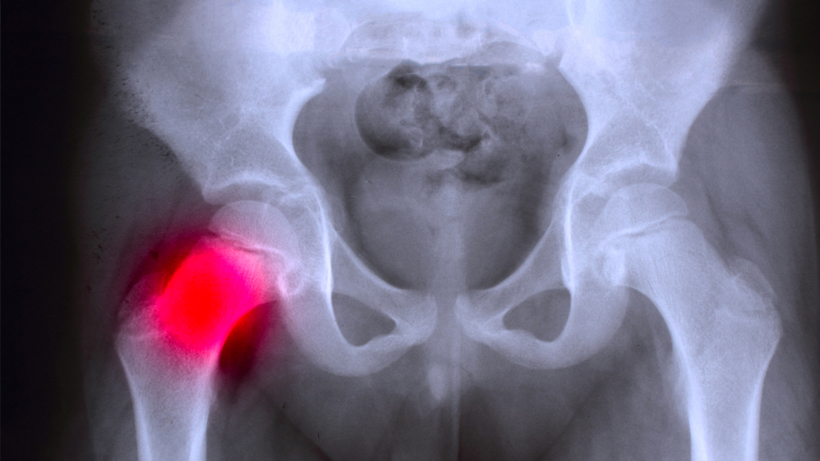

Vrlo je važno što pre dijagnostikovati ovu deformaciju kako bi se što pre preduzele potrebne mere za otklanjanje. U nekim slučajevima moguće je određenim metodama vratiti glavu butne kosti u njeno ležište. Ipak, najpouzdanija dijagnoza postavlja se snimkom, nekada rentgenskim, a danas uglavnom ultrazvukom ili nekom savremenijom metodom.